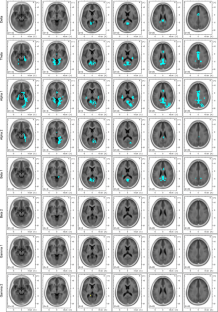

Psilocybin decreased the current source density of neuronal oscillations at 1.5–20 Hz within a neural network comprising the anterior and posterior cingulate cortices and the parahippocampal regions. Most intriguingly, the intensity levels of psilocybin-induced spiritual experience and insightfulness correlated with the lagged phase synchronization of delta oscillations (1.5–4 Hz) between the retrosplenial cortex, the parahippocampus, and the lateral orbitofrontal area.